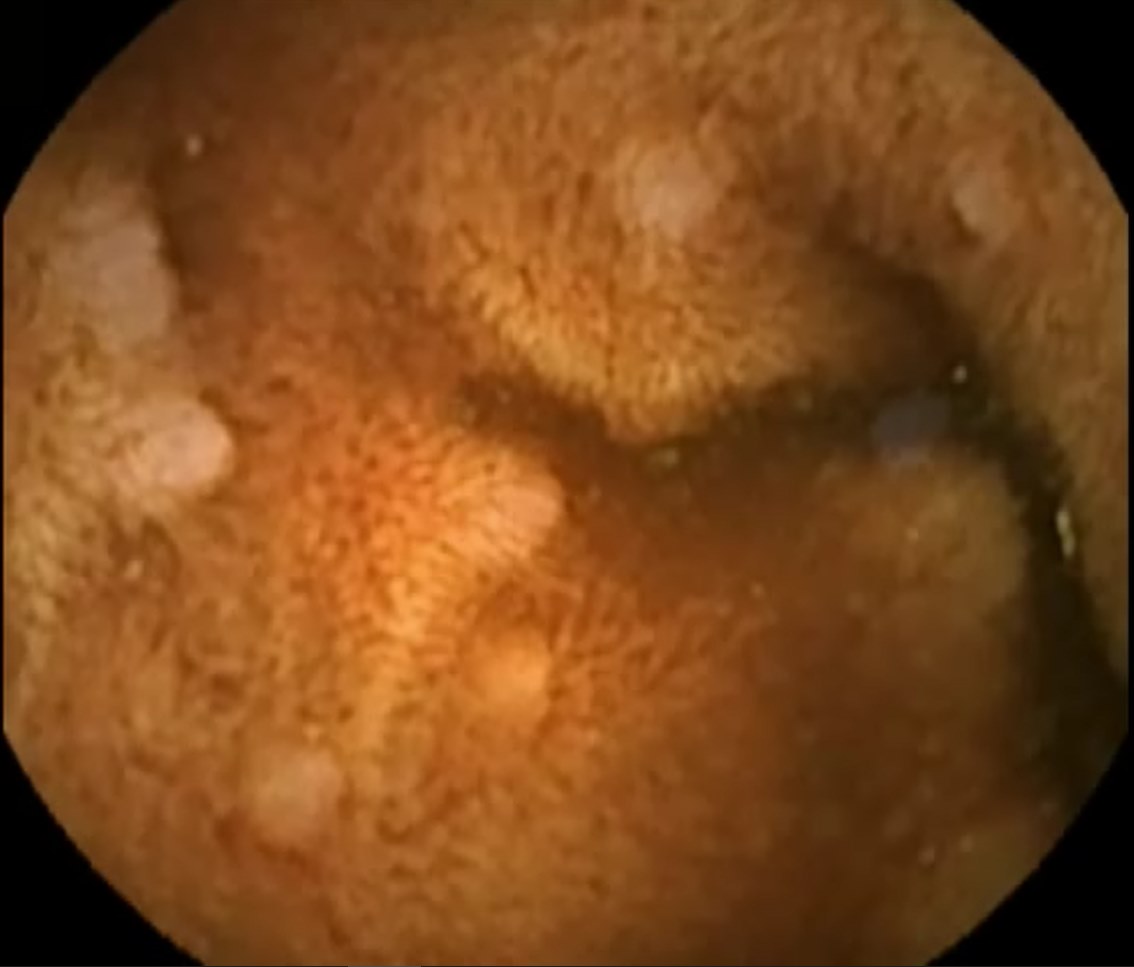

Capsule Endoscopy: Ileum Terminale, Lymphoid Hyperplasia

Capsule Endoscopy: Ileum Terminale, Lymphoid Hyperplasia. Just click on a picture!